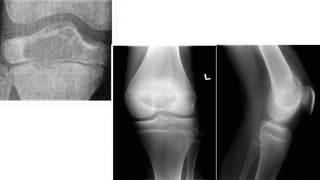

GCT O s t e o c l a s t o m a s

• • Age

• • 20-40 y e a r s

• • L o c a t i o n

• •around the knee: distal femur and proximal tibia: 50-65%

• • distal radius: 10-15%

• • sacrum: 4-10%

• • vertebral body: 5-10%

• A lucent lesion typically situated beneath the articular surface

• E c c e n t r i c

• Narrow z o n e o f transition

• 'soap-bubble' pattern of calcification

• No sclerotic margin

• • overlying cortex is thinned, expanded or deficient

• • Soft-tissue mass may be present

• • No calcification or ossification until complicated by f r a c t u r e

• • CT Scan & MRI

• • To delineate soft tissue extension

• • B o n e s c a n

• • Increased activity in blood-pool phase

Plain film & CT features